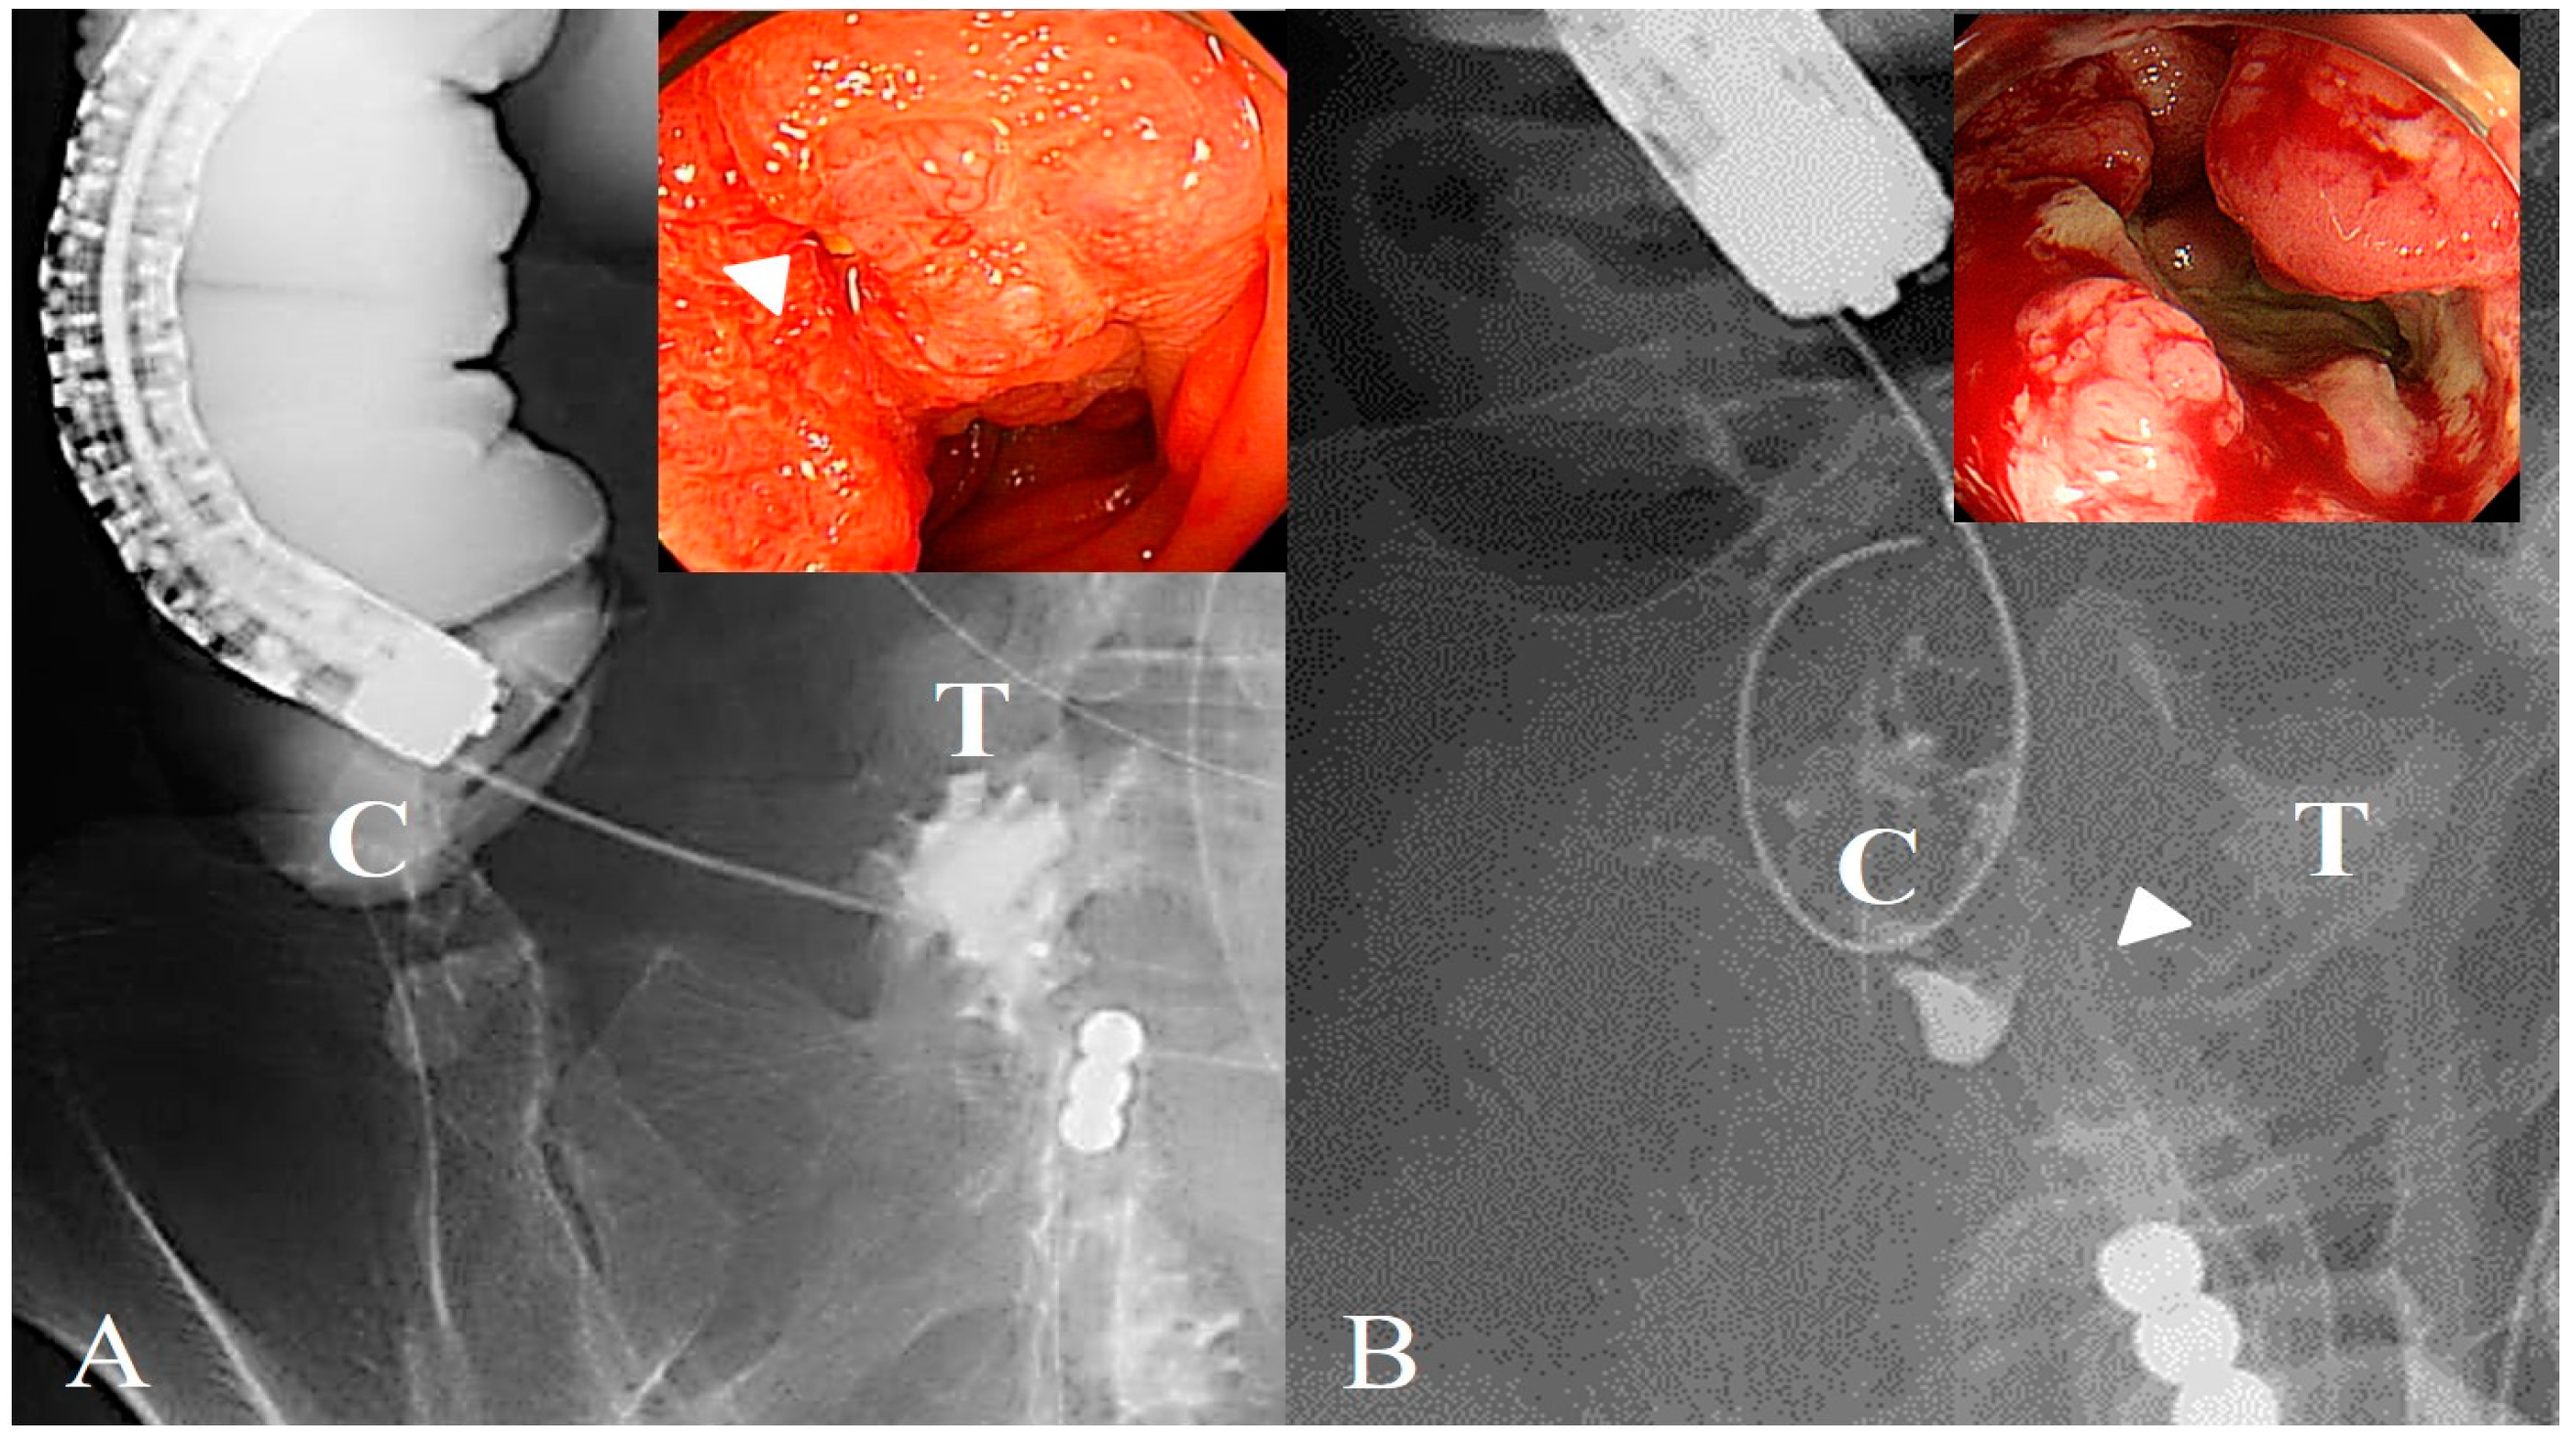

Figure 2. Direct observation of the ileocecal valve obstruction. (A) Shows a typical image of a case in which the stricture site is directly observed. The arrowhead in the figure indicates strictures. A guidewire was passed through the stricture using endoscopic and fluoroscopic imaging techniques. (B) Shows a typical image of a case in which the stricture site is not directly observed. The arrowhead indicates the estimated connection with the ileocecal junction. A guidewire was passed through the stricture under fluoroscopic guidance. C, cecum; T, terminal ileum.

To overcome the challenge of ICVO, we used a strategy involving a two-step procedure for colonic stenting, particularly in cases with severe small-intestine dilation. The first step, inserting a long intestinal tube before colonic stenting, decompressed the dilated small intestine and ensured the safety of the endoscopic procedure. The second step was SEMS placement. If the stricture could not be identified endoscopically (Figure 2) and it was difficult to pass the guidewire through the stricture under endoscopic guidance, contrast media injection or antegrade manipulation through the long intestinal tube facilitated the successful stricture passage of the guidewire (Figure 3).